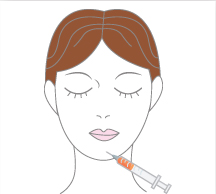

순수 지방을 미세하고 정교하게

이식합니다

함몰 정도가 심하지 않을 경우, 필러를 이용하여 코 옆부터 입술 가장 자리까지 꺼진 부위에 주입하여 불륨을 만들어 줍니다.

함몰 정도가 심하지 않을 경우, 필러를 이용하여 코 옆부터 입술 가장 자리까지 꺼진 부위에 주입하여 불륨을 만들어 줍니다.

가장 간편한 방법으로 시술 수 일상생활에 큰 지장이 없습니다.